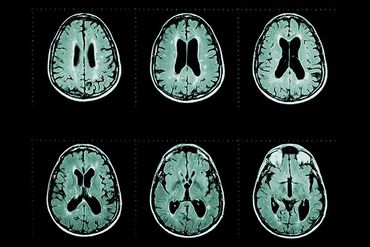

MRI scans can detect disease activity much earlier than physical symptoms. Spotting changes early can help prevent worsening disability by allowing doctors to adjust treatment in time. However, analysing MRI scans is complex, time-consuming, and can be prone to human error.

Multiple sclerosis (MS) is a chronic, disabling disease driven by an abnormal immune response to the central nervous system. Over 120,000 people live with MS in the UK costing the NHS more than £1billiona year. Early disease modifying treatment (DMT) is part of the standard of care for people with MS (pwMS). Unless effectively treated, MS leads to significant disability, and associated care costs, in most cases. However, whether any of the currently licensed fifteen DMTs is effective in an individual person with MS is unpredictable. Effective treatment monitoring is essential to (i) detect signs of disease activity before the individual suffers its effects and (ii) enable early switching to a different, hopefully (more) effective, DMT.

In clinical practice, regular magnetic resonance imaging (MRI) is the only established tool for DMT efficacy monitoring. However, detecting the often subtle changes by inspecting MRI scans is time consuming, tiring and therefore error-prone. icobrain ms is a validated AI technology enabling quantification of MRI datasets, summarising findings in a structured electronic report as well as annotated images highlighting areas of change that help guide assessment. icobrain ms complements visual assessment of MRI scans and helps the clinician to decide whether or not a change in DMT is warranted.

Effective monitoring of sub-clinical disease activity is critical for managing multiple sclerosis (MS). While magnetic resonance imaging (MRI) remains the gold standard for detection, manual visual assessment of scans is time-consuming, prone to human error, and contributes to clinician fatigue.